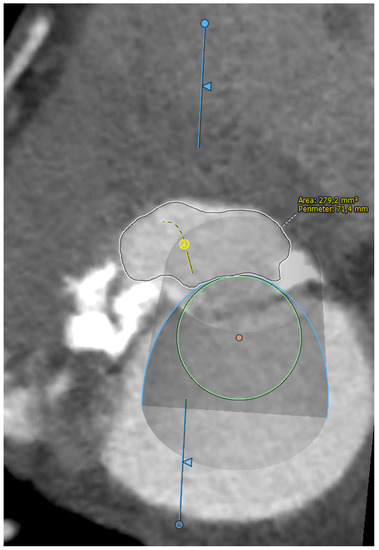

Five observational studies have been published since 2017 exploring the safety and efficacy of ViMAC, all of them with aortic balloon-expandable bioprosthesis in prohibitive surgical risk patients [17,18,19,20,21]. Their designs and main results are summarized in Table 1. To note, the ViMAC procedure shows worse results in terms of technical success and short- and mid-term outcomes than those of ViV and ViR. Indeed, ViMAC is the most challenging percutaneous scenario of all types of TMVR. Mortality at the one-year follow-up is high (around 50%), underscoring the importance of patient selection and of performing these interventions in experienced centers. When comparing the three approaches of TMVR for ViMAC, transatrial appears to have the best results, with one-year rates of mortality at 35% (25% in the latest series) [16,22,23], compared to those of transapical (57%) and transseptal (63%), and higher technical success rates (89% vs. 71% and 65%, respectively). The most important adverse event is the obstruction of the LVOT, with a hazard ratio for mortality of 2.87 (95% confidence interval 1.66–4.96) [19], so this must always be anticipated by a preprocedural CT. An area below 170 mm2 in the LVOT once the valve is implanted (“neo-LVOT”) is highly predictive of this complication (Figure 6) [13]. Other important CT parameters include the angle between the aorta and the LV axis (Figure 7), mitral annulus dimensions (Figure 8), and 2D- or 3D-derived virtual reconstructions (Figure 6).

Figure 6.

“Virtual” valve reconstruction (blue line) and neo-left ventricular outflow tract measurements.

Figure 7.

Angle between the aortic and the left ventricular centerlines (aorto-mitral angulation, 53o), predictive of left ventricular outflow tract obstruction.